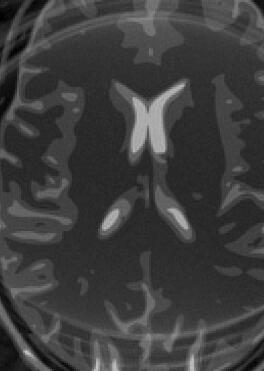

Fig. 14 exhibits the reconstruction results with the spiral trajectory with for . The reconstructed images are displayed alongside profile plots of row . The same is also presented in Figures 13 for .

When sampling on a spiral trajectory, SPURS further demonstrates its superior performance over the other methods. For values high enough, SPURS, NUFFT and rBURS with achieve very good results, but the performance curve for each method levels off for different values of (Figures 9, 10, 11 and 12). Iterative SPURS levels off for values as low as , requiring about iterations to converge to its best result. For these low values, significant artifacts appear in the reconstructed image produced by all methods excluding SPURS as presented in Fig. 13 for and Fig. 14 for . The performance curve of the NUFFT method and of a single iteration of SPURS level off at around . For and higher, a single iteration of SPURS produces marginally better results than those produced by NUFFT, which requires about iterations to converge. Among the other non-iterative methods, both rBURS with and convolutional gridding perform similarly well for , however the results are still inferior to those of a single iteration of SPURS, all of which have similar computational complexity.